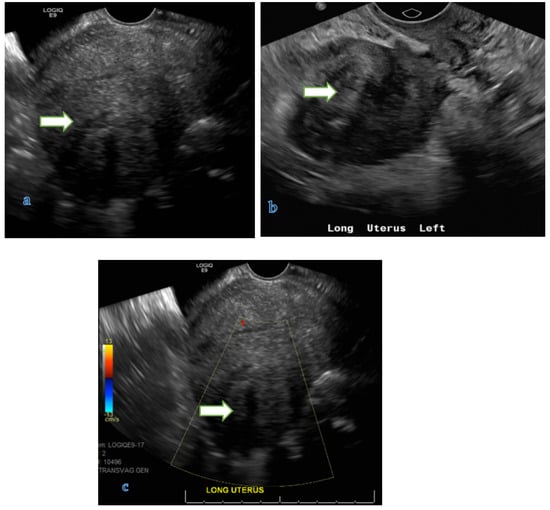

4.1. Ultrasound

- Ultrasound is usually the primary modality to evaluate women with pelvic symptoms. It has the advantages of wide availability, feasibility, and cost-effectiveness with no radiation hazards. Limitations include operator dependence, limited field of view, and low contrast resolution